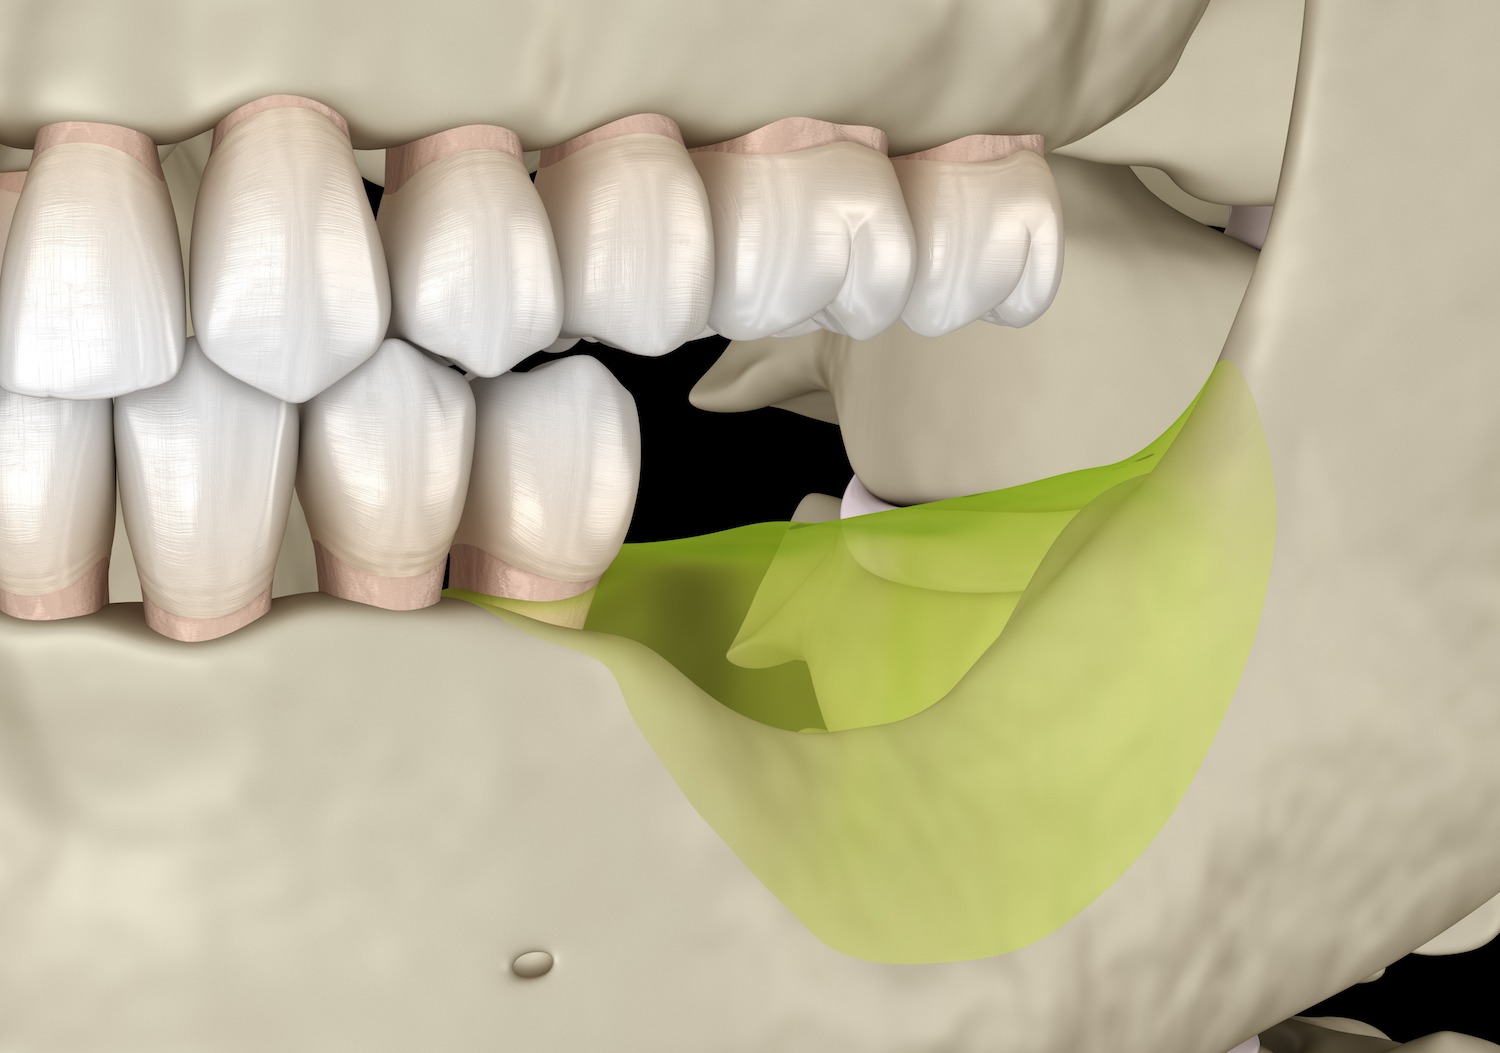

GBR法

骨の厚みや高さを補いたい部分をメンブレンと呼ばれる人工膜で覆い、その中に骨補填剤(人工骨など)を詰めて、骨の再生を促します。骨補填剤を使用せず、自家骨(自身の他の部位の骨)を移植することも可能です。

サイナスリフト

サイナスリフトは、残っている骨の量が5mm以下の場合に適用される骨造成術です。歯が生えていた箇所の側面の歯ぐきを切開し、骨に穴を開け、そこに骨補填剤を詰めていきます。ソケットリフトと比べて大掛かりな手術になりますが、その分だけ再生できる骨の量も多いです。